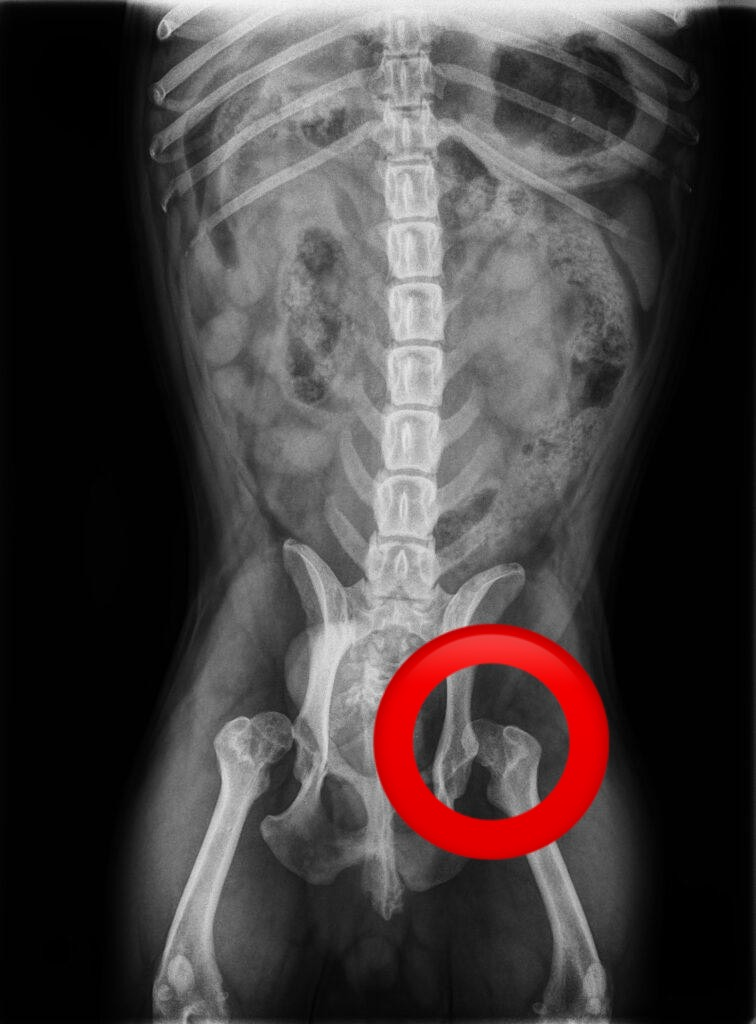

検査を進めていくと実は両方の股関節が脱臼していました。

股関節は、「骨盤側の寛骨臼」と「大腿骨の骨頭」がボールとポケットのようにはまり込んで構成されています。この構造があるからこそ、スムーズな歩行や走行が可能なのです。

しかし、この連結部分が外れてしまうことを股関節脱臼(こかんせつだっきゅう)と呼びます。